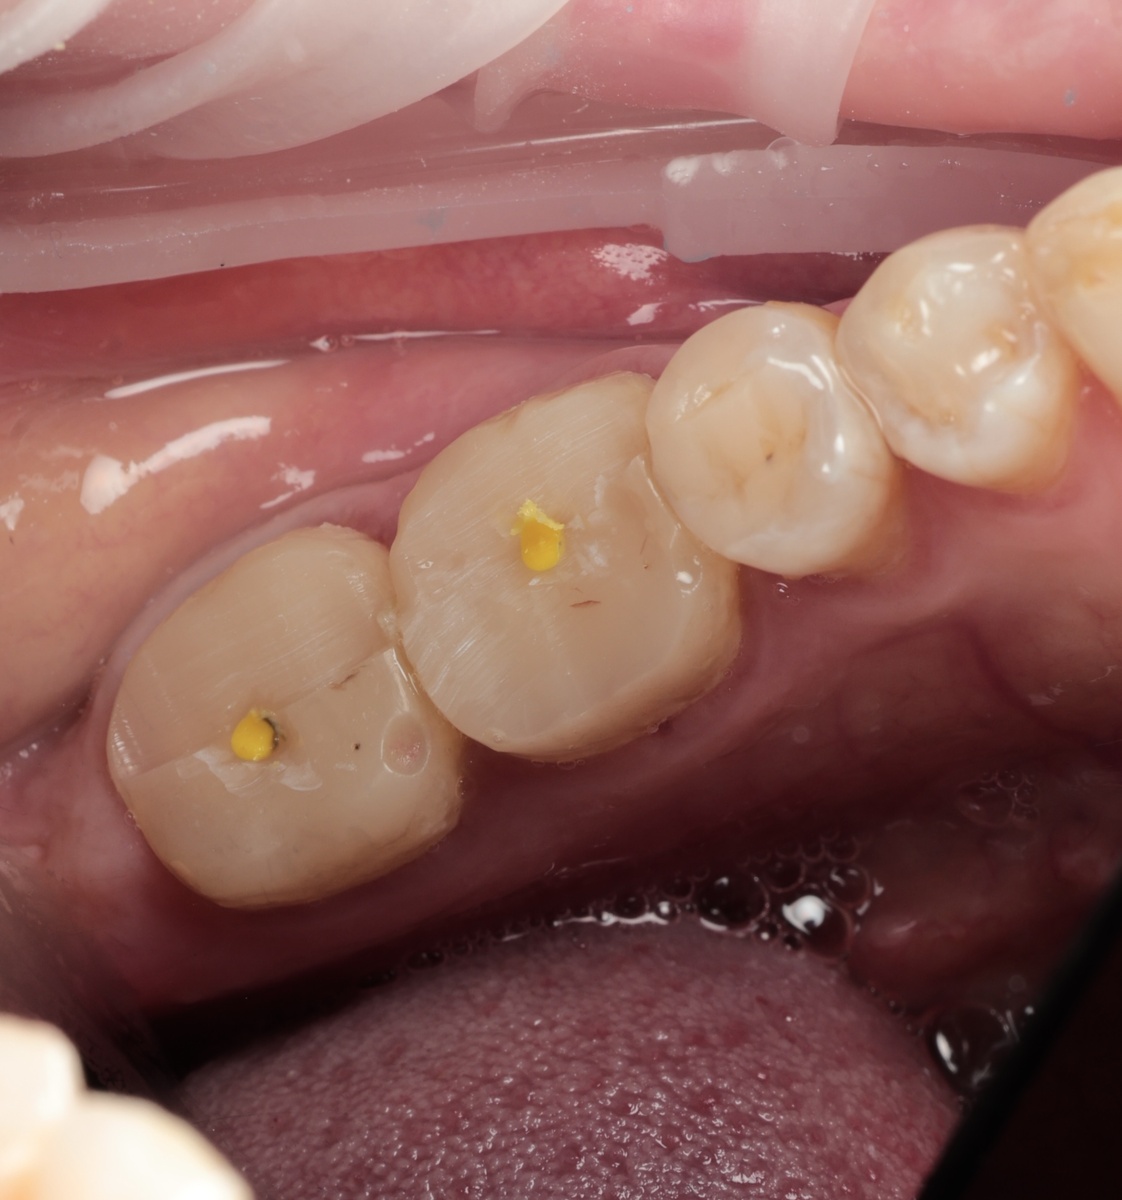

"Билдап", выполненный в другой клинике - с этим пациентка обратилась к нам

Каналы запломбированы хорошо, периапикальных изменений нет. Казалось бы, работа ожидается простая - установить коронки и всё. Плёвое дело. Смущали только жёлтые штифты.

При обработке зубов под коронки произошло неожиданное. То, что должно было быть билдапом (композитной пломбой, адгезивно прикреплённой к тканям зуба - намертво), просто отлетело, играючи. Странные жёлтые штифты тоже без проблем покинули зубы.